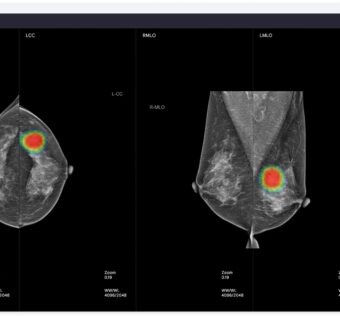

DistilINFO Hospital IT - (Tuesday November 7, 2023) Pioneering research highlights AI’s proficiency in diagnosing heart valve disease and predicting cardiovascular risks with notable accuracy. One study validates an AI-enabled digital stethoscope’s superiority over traditional methods, achieving a 94.1% detection rate. Another… ![]() Lunit to Unveil AI Cancer Diagnostics Studies at RSNA

DistilINFO Hospital IT - (Tuesday November 7, 2023) At RSNA 2023, Lunit will display seven AI studies aimed at enhancing diagnostic efficiency in chest radiography and breast cancer risk evaluation. The presentations will showcase advancements like AI algorithms that improve the accuracy… |